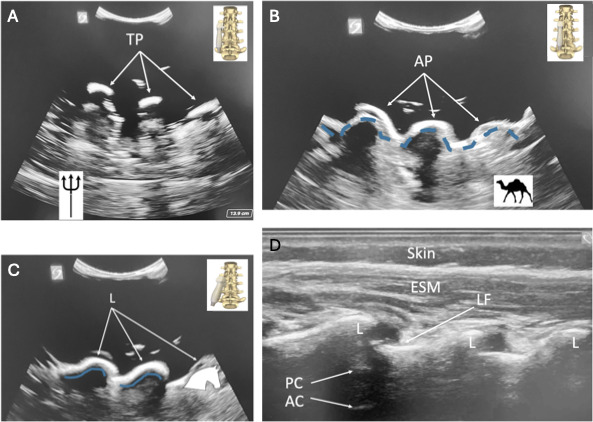

Unlabelled: Opportunities to learn ultrasound-guided/assisted (USGA) neuraxial techniques for pediatric patients are limited, given the inherent high stakes and small margin of error in this population. Simulation is especially valuable in pediatrics because it enhances competency and efficiency, without added risk, when learning new skills, specifically those seen with ultrasound-guided regional anesthetic techniques. However, access to simulation opportunities involving the use of phantom models in medical education is limited due to excessive costs. We describe a process for producing ultrasound phantoms by using synthetic ballistic gelatin; these ultrasound phantoms can be used for simulation and are affordable, reproducible, and indefinitely shelf stable. The ultrasound images produced by these phantoms are comparable to those obtained from a real pediatric patient, including the sacral anatomy necessary for caudal epidural blocks, as validated by practicing pediatric anesthesiologists. Phantom models offer a more cost-effective alternative to commercially prepared phantoms, thereby expanding access to realistic simulations for neuraxial ultrasound in pediatric medical education, without the prohibitively high expense.